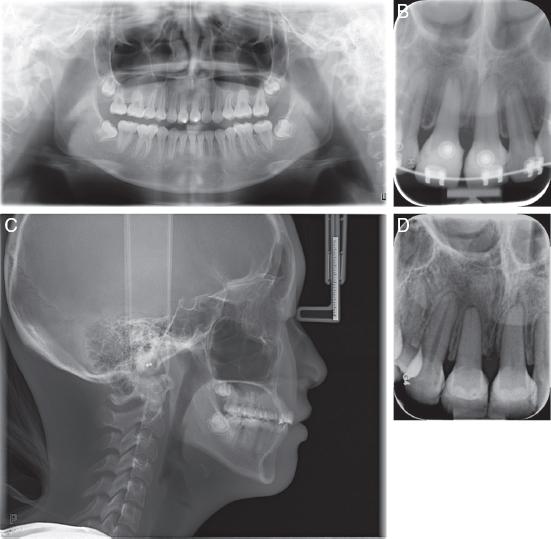

An 11-year-old healthy girl visited the clinic with the chief complaints of an uneven smile, after suffering dental trauma to her upper incisors (Figure 7A-H). The upper right lateral incisor (#12) and upper left central incisor (#21) had been subluxated, while the upper right central incisor (#11) suffered a complicated crown fracture which extended subgingivally. Teeth #12 and #21 were root canal treated and displayed radiographic evidence of progressive replacement resorption, while #11 was decoronated 2 mm below the cemento-enamel junction for alveolar bone preservation (Figure 8A-D). She was referred by the paediatric dentist for multidisciplinary management and extractions of #12 and #21, after infra-occlusion of these teeth was observed.

(A) Pretreatment panoramic radiograph. (B) Periapical radiograph showing decoronated #11 and crown attached; Resorption on the apical surfaces of #12 and #21. (C) Lateral cephalogram. (D) CBCT section showing developing tooth #35 with ⅔ root length and (E) Developing tooth #45 with ¾ root length.